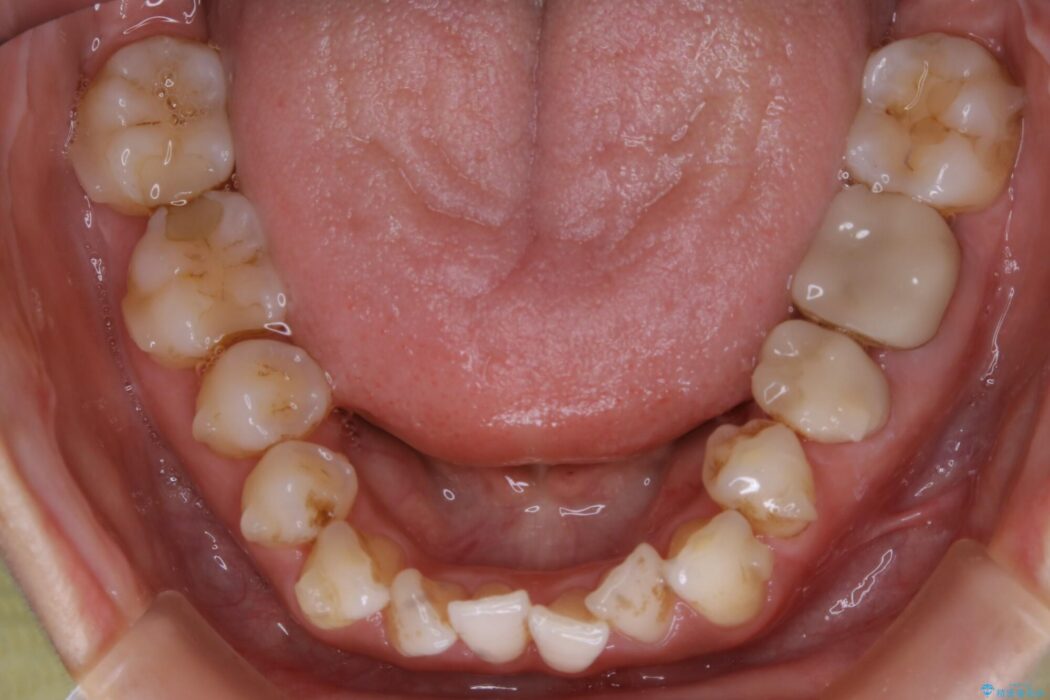

ガタガタした歯列の見栄えが悪く歯磨きがしづらいとのことで来院されました。

検査したところ歯の叢生自体は歯列幅の拡大やディスキング(IPR)で解決できる範囲内でした。

ですが、上顎左側の歯が前方へ寄っている状態であるため噛み合わせにズレが生じていました。